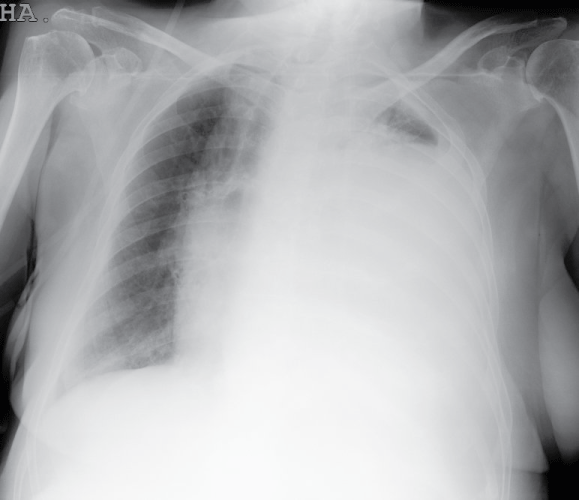

Chest radiograph showed the presence of a left pleural effusion occupying two thirds of the hemithorax (Figure1). A thoracocentesis was performed and 800 cc of green-colored pleural fluid was drained. Biochemical analysis of pleural fluid showed a pH level of 7.28, WBC count of 130/mm3 with 65% of neutrophils, glucose of 144 mg/dL, total protein of 5.8 g/dL (total protein level in serum of 6.2 g/dL), LDH of 2551 U/L (LDH level in serum of 443 U/L), bilirubin 5.8 mg /dl (plasma 0.4 mg/dl) and amylase 47 U/L. The bilirubin ratio pleural fluid/serum was 14.5.